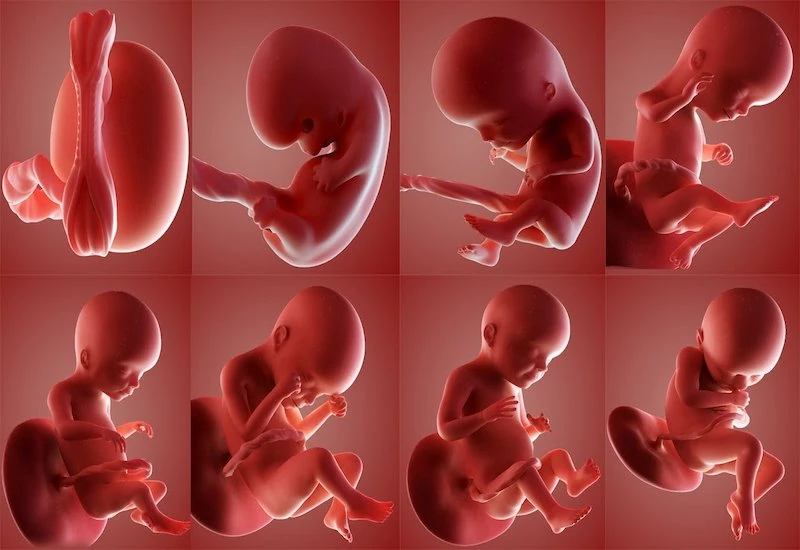

Thời điểm thực hiện siêu âm thai 4D

Chọn thời điểm siêu âm 4D là một yếu tố quan trọng trong việc đảm bảo có được những thông tin chính xác và hữu ích cho cả mẹ và bé. Khả năng cung cấp hình ảnh chi tiết và nhiều chiều của siêu âm 4D cho phép bác sĩ quan sát tốt hơn sự phát triển của thai nhi ở mỗi giai đoạn cụ thể trong thai kỳ. Việc chọn đúng thời điểm không chỉ mang lại lợi ích trong việc phát hiện sớm các bất thường mà còn tăng cường nhiệm vụ của bác sĩ trong việc định hướng chăm sóc sức khỏe thai nhi. Sự đúng thời điểm còn giúp cho hình ảnh được rõ nét và sống động hơn, tạo trải nghiệm cảm xúc mãnh liệt cho gia đình trong quá trình chào đón thành viên mới.

Thời điểm siêu âm 4D ảnh hưởng quan trọng đến chất lượng hình ảnh và độ chính xác của thông tin chẩn đoán. Các chuyên gia khuyến cáo thường có ba giai đoạn “vàng” thích hợp để thực hiện siêu âm thai 4D, mỗi giai đoạn đóng góp vào một khía cạnh khác nhau của sự phát triển thai nhi.

Ở khoảng tuần thứ 11-13, siêu âm 4D được sử dụng để đo độ mờ da gáy, một chỉ số quan trọng giúp phát hiện sớm các nguy cơ bất thường về mặt di truyền như hội chứng Down. Vào thời điểm này, cấu trúc cơ thể của thai nhi vẫn đang trong giai đoạn hình thành, việc thực hiện siêu âm không chỉ giúp xác định tuổi thai mà còn cung cấp thêm nhiều thông tin giá trị giúp định hướng chăm sóc thai kỳ.

Tại mốc tuần 20-22, siêu âm 4D trở thành “cánh tay đắc lực” trong việc khảo sát chi tiết các cơ quan nội tạng của thai nhi. Giai đoạn này giúp bác sĩ nhận diện các bất thường trong sự phát triển của nội tạng, từ đó can thiệp hoặc quản lý sớm hơn để đảm bảo sự phát triển lành mạnh cho bé.

Cuối cùng, từ tuần 30-32, siêu âm 4D tiếp tục được sử dụng để đánh giá sự phát triển tổng thể và phát hiện các vấn đề muộn. Tại thời điểm này, hình ảnh siêu âm 4D cho thấy kích thước và tầm vóc thai nhi, đồng thời giúp bác sĩ theo dõi sát hơn xem những kế hoạch trước đó có đang đi đúng hướng hay không.